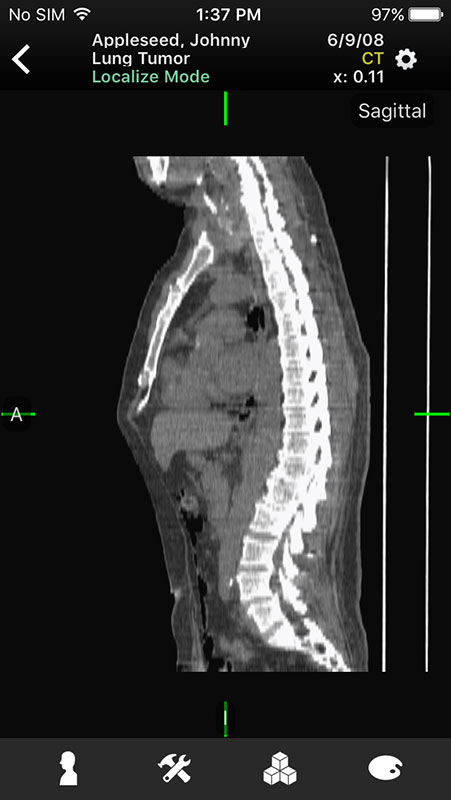

Just like in Mobile MIM app, images open in multi-planar view allowing users to choose series depending on the type of imaging technique, add annotation, or measure the image.

For example, flicking screen right or left enables users to switch between series, planes, and images, while swiping up and down switches between planes, or images in the series (with 2D images).

Swiping across the screen at regular speed adjusts the contrast of the image, whereas right/left changes the level, and up/down changes the window.